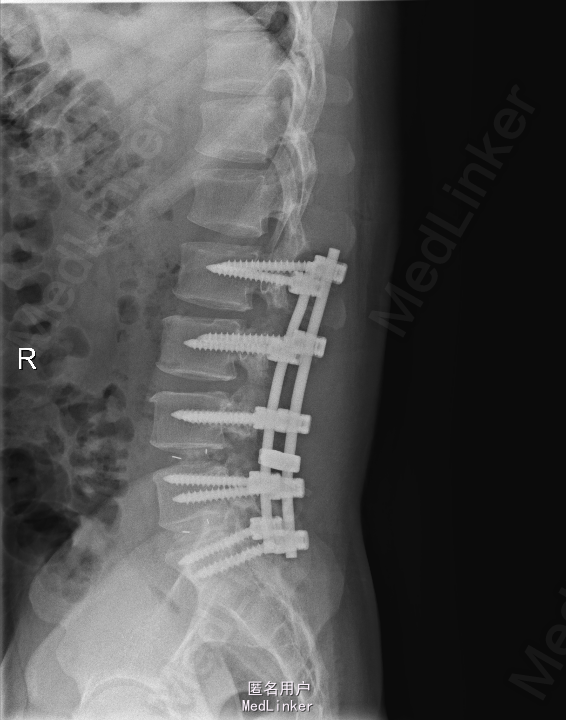

查体:腰部叩痛,腰部活动受限,左侧膝内侧、小腿外侧、内踝、足部感觉减退,右侧小腿、足背感觉减退,屈髋、伸膝、踝背伸肌肌力左侧4级,右侧4-5级,踇背伸、跖屈肌肌力左侧3-4级,右侧4级,双侧膝腱反射+,跟腱反射+,双侧巴氏征阴性,直腿抬高试验左侧40°阳性,右侧阴性。 辅助检查: X-ray:腰椎退行性变,多节段不稳 CT:腰椎间盘突出并椎管狭窄伴钙化,腰2-3,3-4,4-5,腰5骶1 MR:腰椎间盘突出并椎管狭窄,腰2-3,3-4,4-5,腰5骶1 上传受限无法全部上传,见谅

诊断:腰椎间盘突出症并椎管狭窄 处理:1、完善相关辅助检查,明确诊断,有无手术指证; 2、完善手术评估,有无手术禁忌,手术风险及并发症; 3、在全麻下行腰椎后路多节段减压椎间植骨融合内固定术 4、腰2-3,腰3-4行开窗减压,腰4-5,腰5-骶1行椎间Cage植骨融合

随访:1、应常规术后1个月、3个月、半年随访; 2、术后患者腰痛较前减轻,下肢麻木感觉较前好转,下肢活动较前有力,屈髋、伸膝、踝背伸肌肌力左侧4级,右侧4-5级,踇背伸、跖屈肌力左侧4级+,右侧4-5级,左侧肢体抬高试验阴性。 讨论:1、多节段腰椎间盘突出,手术指证把握 2、责任节段的确立,以影像学间盘突出节段为依据,还是联系临床表现? 3、手术节段的确立,以影像学与临床表现确立责任节段间盘为依据,还是术中探查为金标准? 4、多节段间盘突出,开窗髓核VS椎间植骨融合? 5、开窗髓核与椎间植骨融合相结合,如何确定融合节段与开窗节段? 6、多节段内固定,腰椎活动度影响,稳定与腰椎活动功能的平衡?